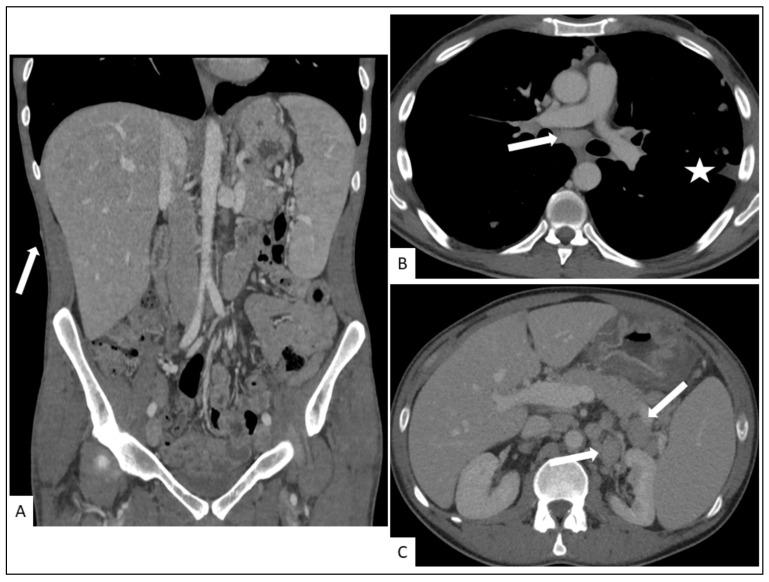

卡波西肉瘤(KS)是一种与免疫抑制相关的罕见非典型恶性肿瘤,可被视为一种机会性肿瘤,对免疫调节或恢复有反应。已确定有四种不同的流行病学形式(艾滋病相关型、医源性、地方性或经典型KS)。虽然临床检查足以诊断KS的皮肤病变,但为了检测累及其他器官的病变,还需要进行额外的检查。近年来,已开发出新的组织学标志物用于检测病变中HHV-8潜伏或裂解蛋白,在临床诊断存疑时有助于确诊。最近,局部免疫反应的评估也已显示在必要时为选择合适的治疗方案提供一些指导。我们还综述了传统放射影像学以及诸如F-氟脱氧葡萄糖正电子发射断层扫描、热成像和激光多普勒成像等非侵入性成像工具在KS诊断及需要全身治疗患者的治疗反应随访中的应用指征和结果。